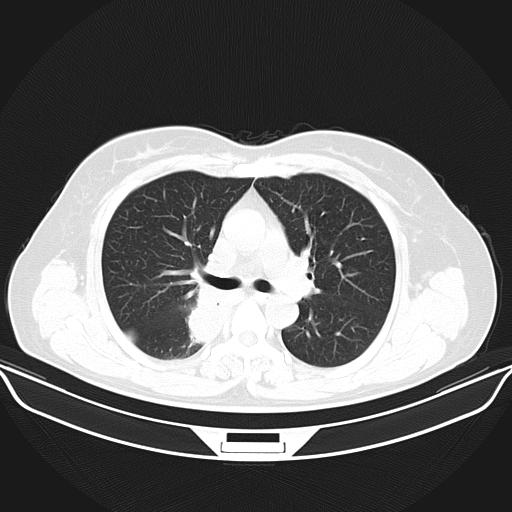

标题: CT22224:肺部肿块

f,48,主因咳嗽咳血来我院检查,无发热。

1)右肺下叶背段团块状软组织密度影;建议抗炎治疗后复查排除肿瘤性病变。2)右侧少量胸腔积液。